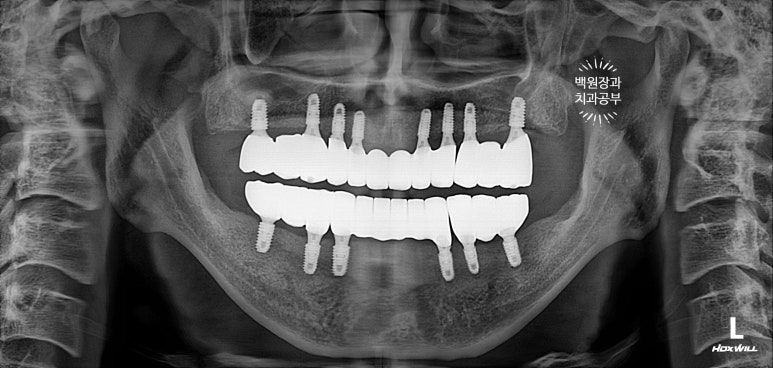

이렇게 위에는 8개의 임플란트가, 아래에는 6개의 임플란트가 예쁘게 식립된 것을 보실 수 있을겁니다.

깔끔하게 완성된 보철물은 치과용 파노라마 사진에서 확인하실 수 있고,

비전공자가 보아도 나란히 가지런한 임플란트는 편안함을 줍니다.

6개월 체크업 시간에 한 번 더 교합을 비롯한 사용 후기를 확인해야 합니다.

똑같아 보일 수 있으시겠지만, 6개월이 지난 후 치과용 파노라마 사진입니다.

보통 임플란트의 초기 실패는 6개월 정도 안에 발견할 수 있기에, 이 시기에 한 번 더 오셔서 체크해보는 것이 중요합니다.

필요하면 치아의 크기나, 교합을 수정하기도 합니다.

한 번 완성 된 임플란트는 무조건 영원히 쓸 수 있는 것은 아닙니다. 자기 치아처럼 주기적으로 엑스레이도 찍고, 스케일링도 해주면서 소중히 관리하셔야 합니다.!!